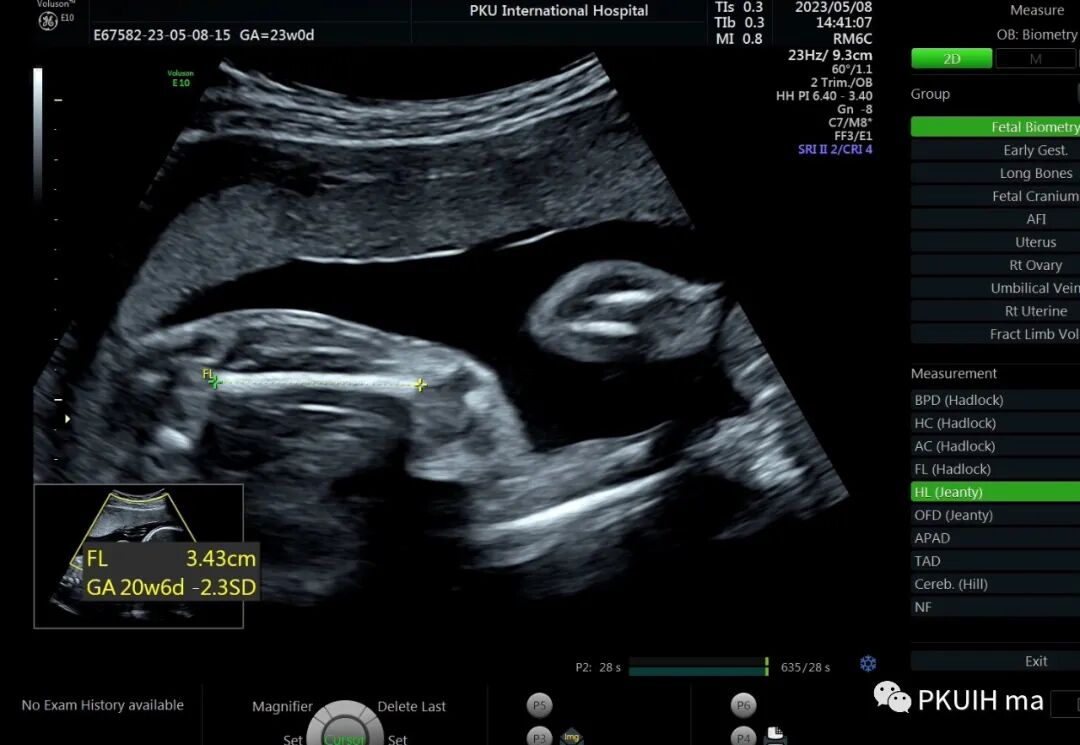

孕23周常规筛畸发现四肢长骨偏短,孕妇月经正常,核对早孕超声,孕周也没问题。

24周+复查发现还是肢体短,生长变慢

大多数孕期发现的骨骼发育不良通常表现为严重的短肢畸形,但足底长度通常不受累。正常时股骨长/足底长度约1:1,<0.87,考虑骨骼发育不良,同时在FGR的诊断中也有帮助。产前超声诊断的主要目的是识别出致死性的骨骼系统发育异常,对临床起到指导意义。区分致死和非致死性骨骼发育异常的主要超声指标有:1、严重的四肢短肢畸形,四肢所有长骨均低于该孕周平均值4个标准差,或股骨长度/胸围<0.16。2、严重的胸廓狭窄:胸围<胎龄的第5百分位,心胸比>0.6(一定要先除外心脏畸形),胸围/腹围比<0.89。3、某些特殊征象,比如严重的颅骨“三叶草样”畸形。